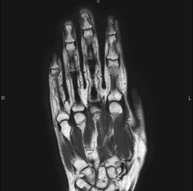

Exploración para el estudio de lesiones en tendones, ligamentos y pequeñas articulaciones. Es la prueba que mejor permite diagnosticar las frecuentes capsulitis por traumatismo, la artrosis y las roturas de tendones. Tiene una duración aproximada de 20 minutos. No emplea radiación ionizante. - RM Caderas